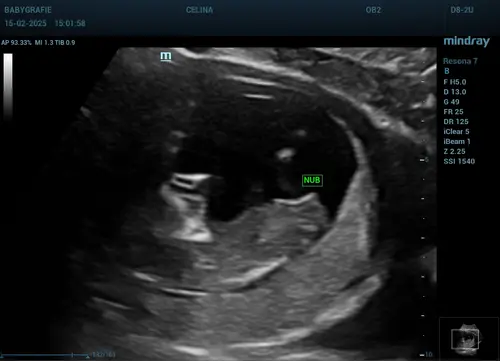

Iemand een gokje echo is op 12w3d geweest :) donderdag nipt test doen :)